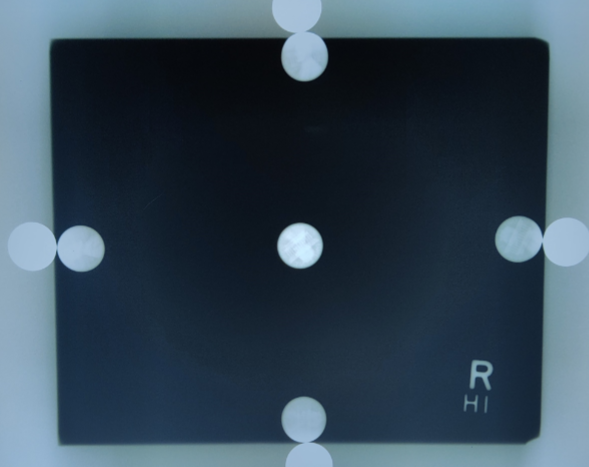

What is this test?

Collimator penny test. Used to verify collimator field accuracy within ±2% of SID.